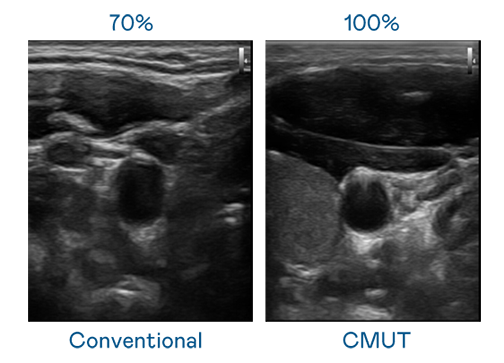

CMUT 技術是一種用電容式微機電元件來產生超音波訊號的技術。與傳統 PZT 壓電式技術相比,CMUT 頻寬增加 30%,更寬頻的超音波訊號讓影像解析度大幅提升,是實現高影像品質醫療超音波掃描、促進精準醫療發展的關鍵技術。

大頻寬帶來超清晰影像

超音波影像的解析度高低,首先取決於探頭能發出的訊號頻寬。至尊国际 CMUT 可提供高清晰的超音波訊號,提供高頻寬、高靈敏度、影像紋理細節更高的超音波影像,協助醫護人員縮短影像判讀時間及利用精準的醫療影像進行診斷。